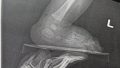

手術後に夫が面会に来てしばらく滞在しましたが、息子は麻酔がまだ残っているのか滞在時間中はずっと眠っており起きませんでした![]()